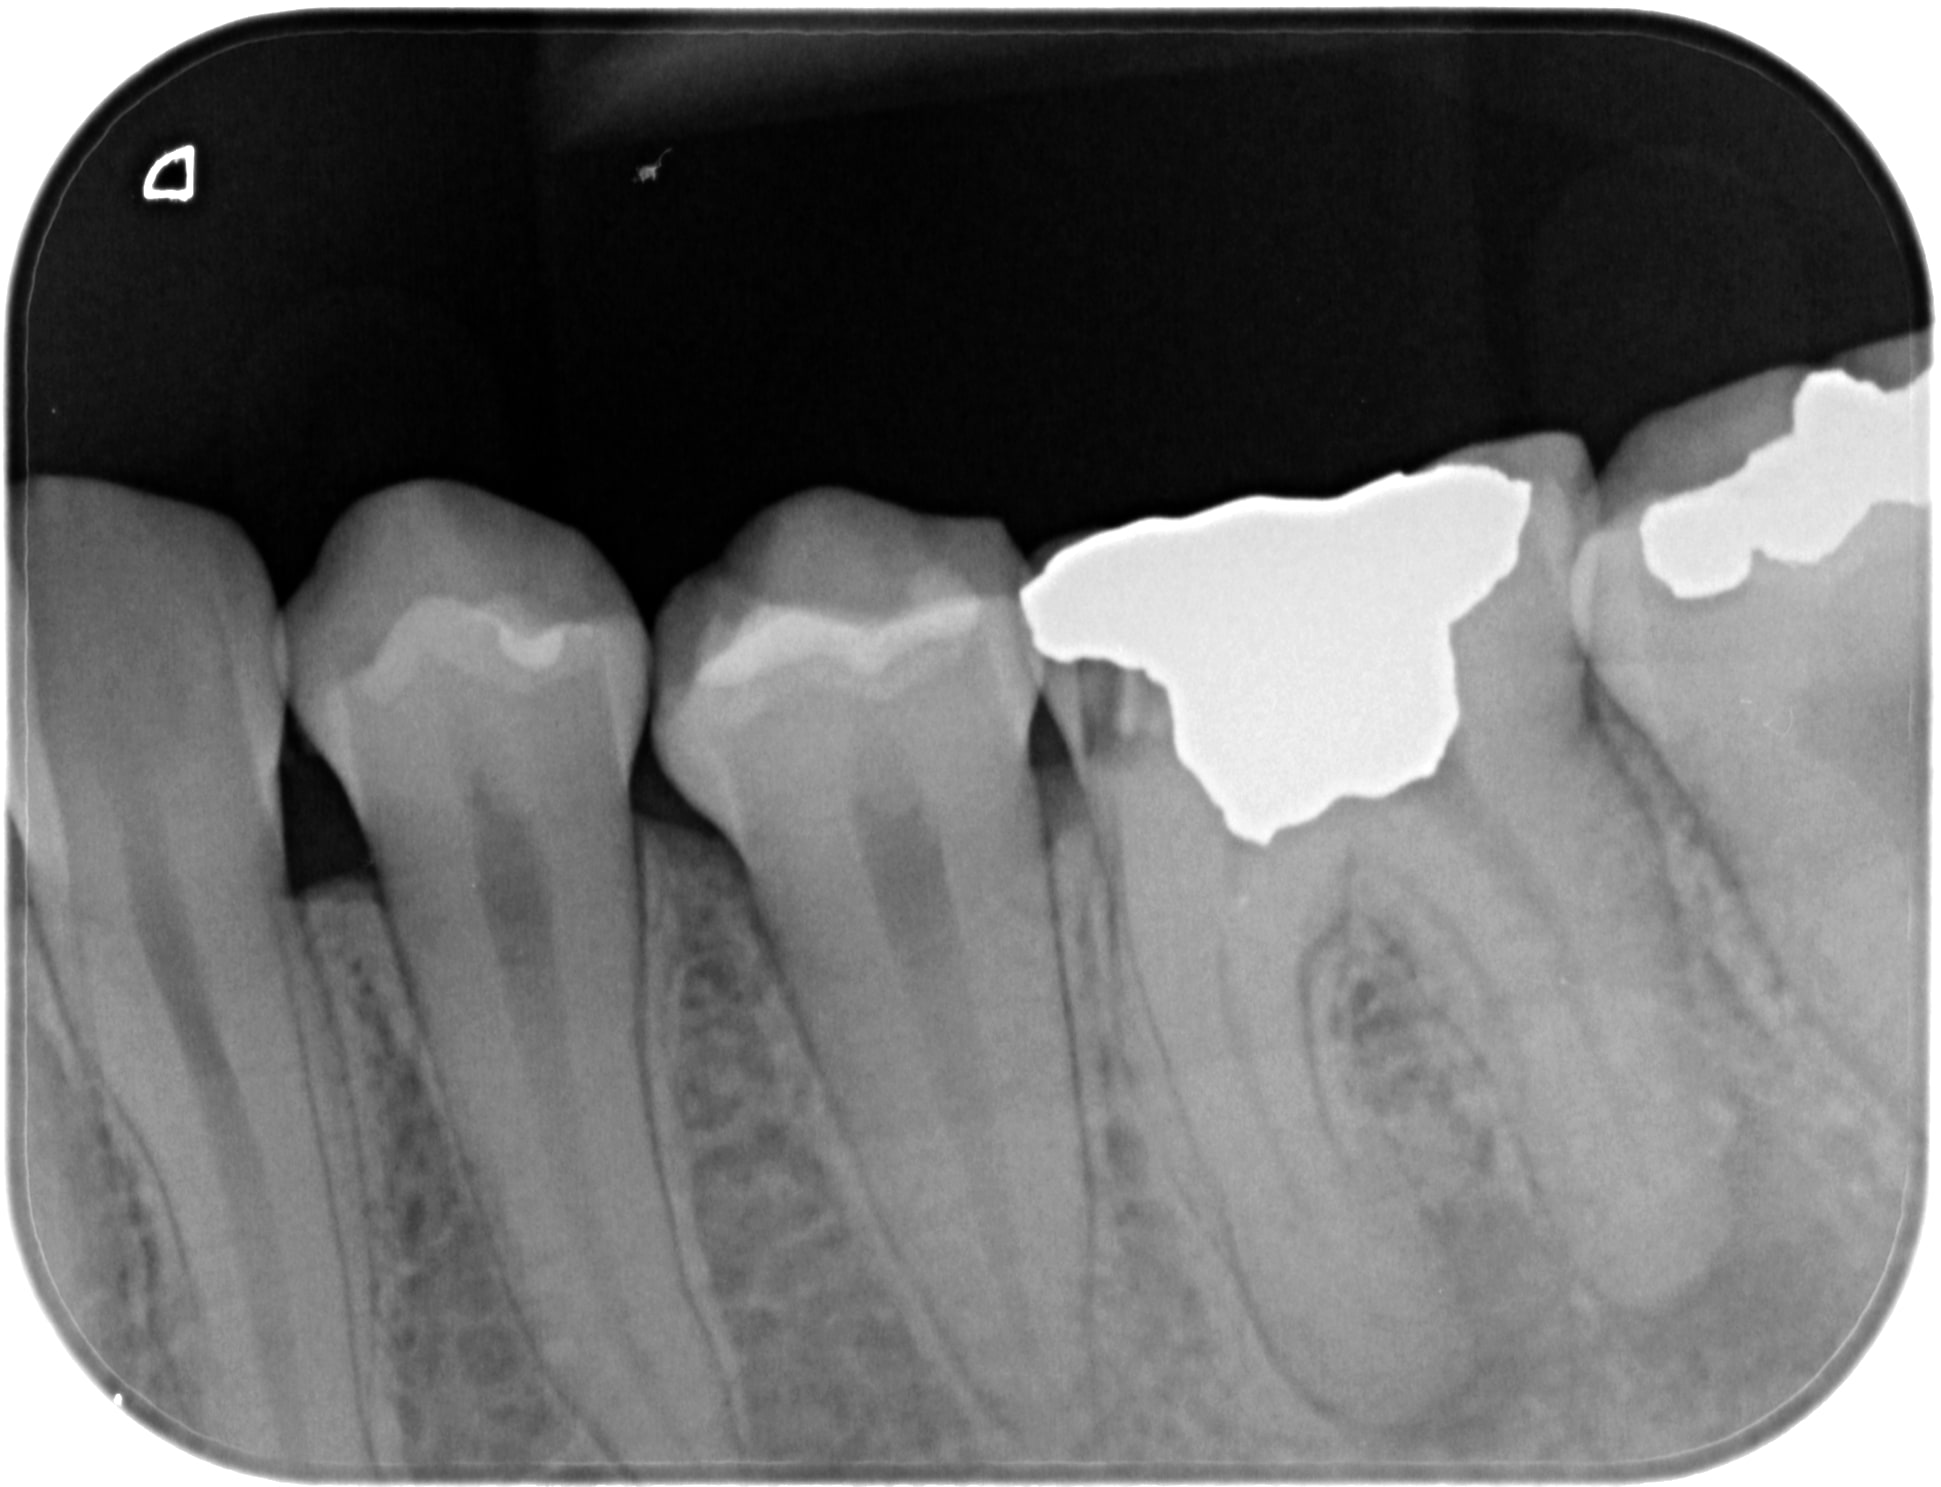

Spécial dédicace au "blanc" en mésial de la 7 derrière une cc... logique implacable ;)